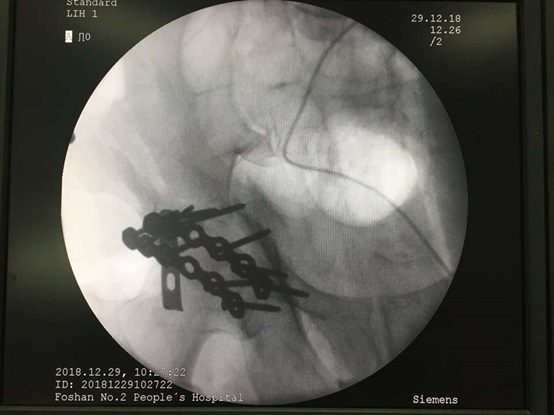

随后,邱主任团队在此漂亮体位的基础上,选择合适切口位置,游刃有余地下刀、分离组织、复位骨折处、钢板螺钉固定…